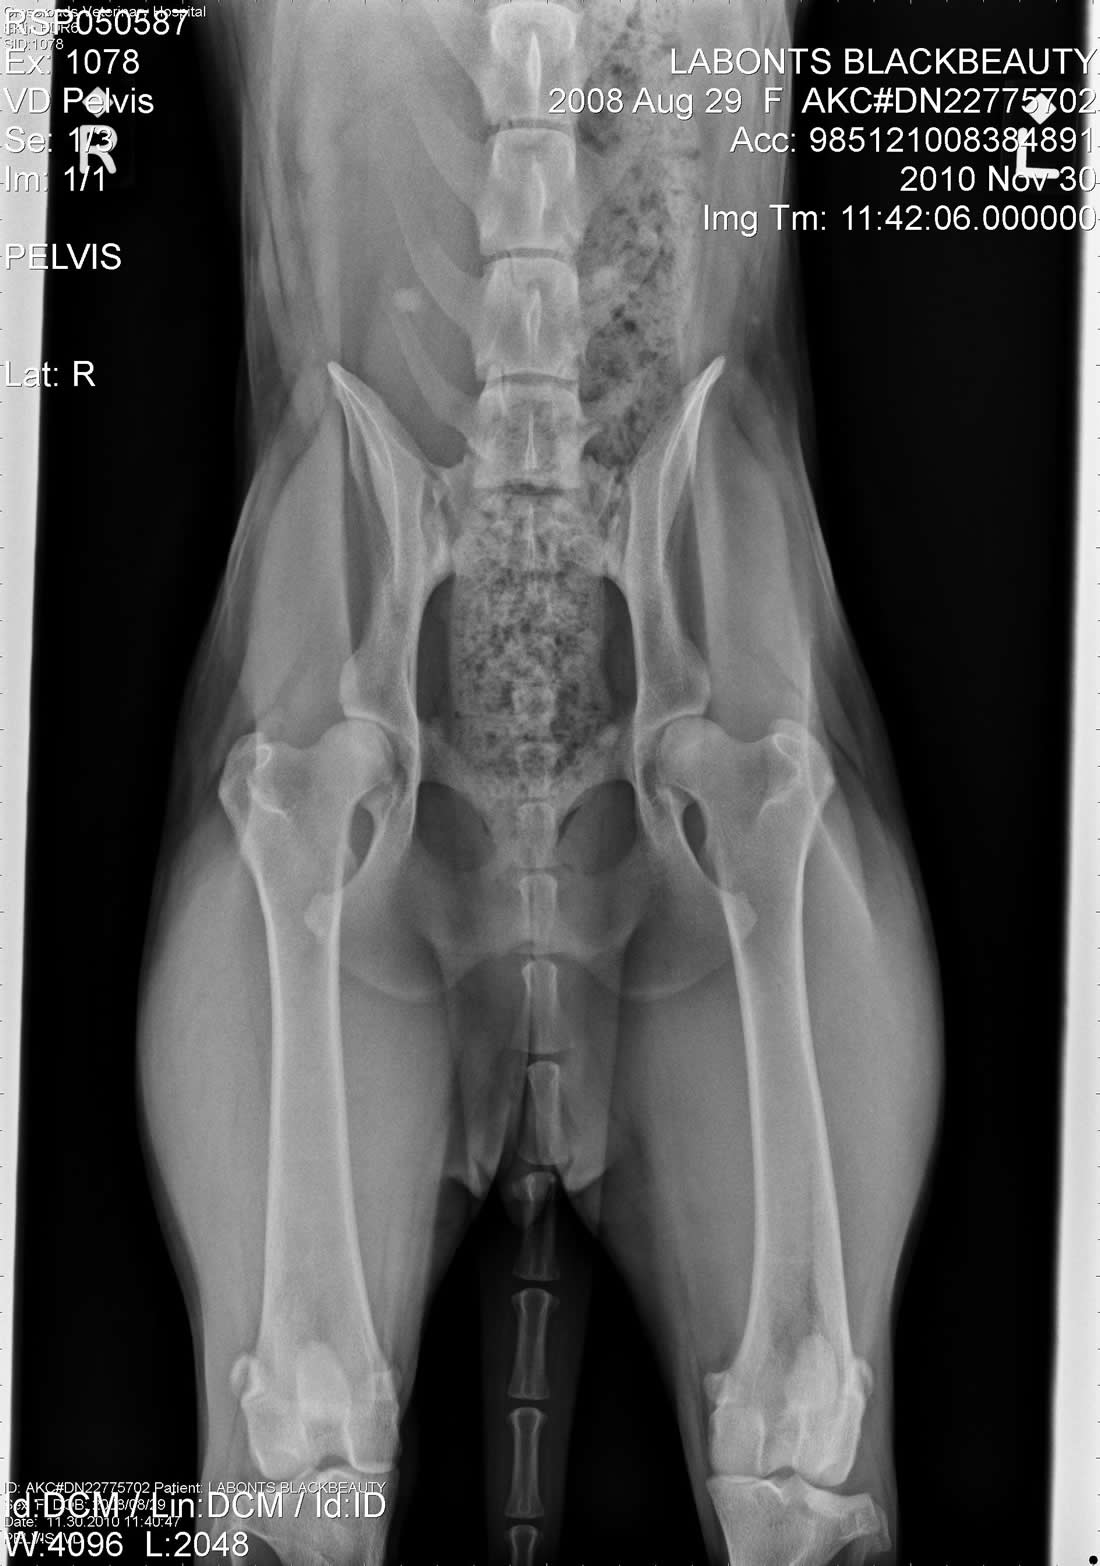

Tilly OFA - Female Working German ShepherdLabonte's Black Beauty (Tilly) OFA Excellent is an extreme prey driven dog. Her hips have the rare OFA rating of Excellent. She is black and has an awesome muscular European structure. Tilly pedigree is nothing short of awesome. With dogs like Fero, Quinto, Orry and lines like Karthago, Antverpa, Tiekerhook, Korbelbach giving her a very well rounded foundation and strong genes for breeding. Click here for Tilly's pedigree